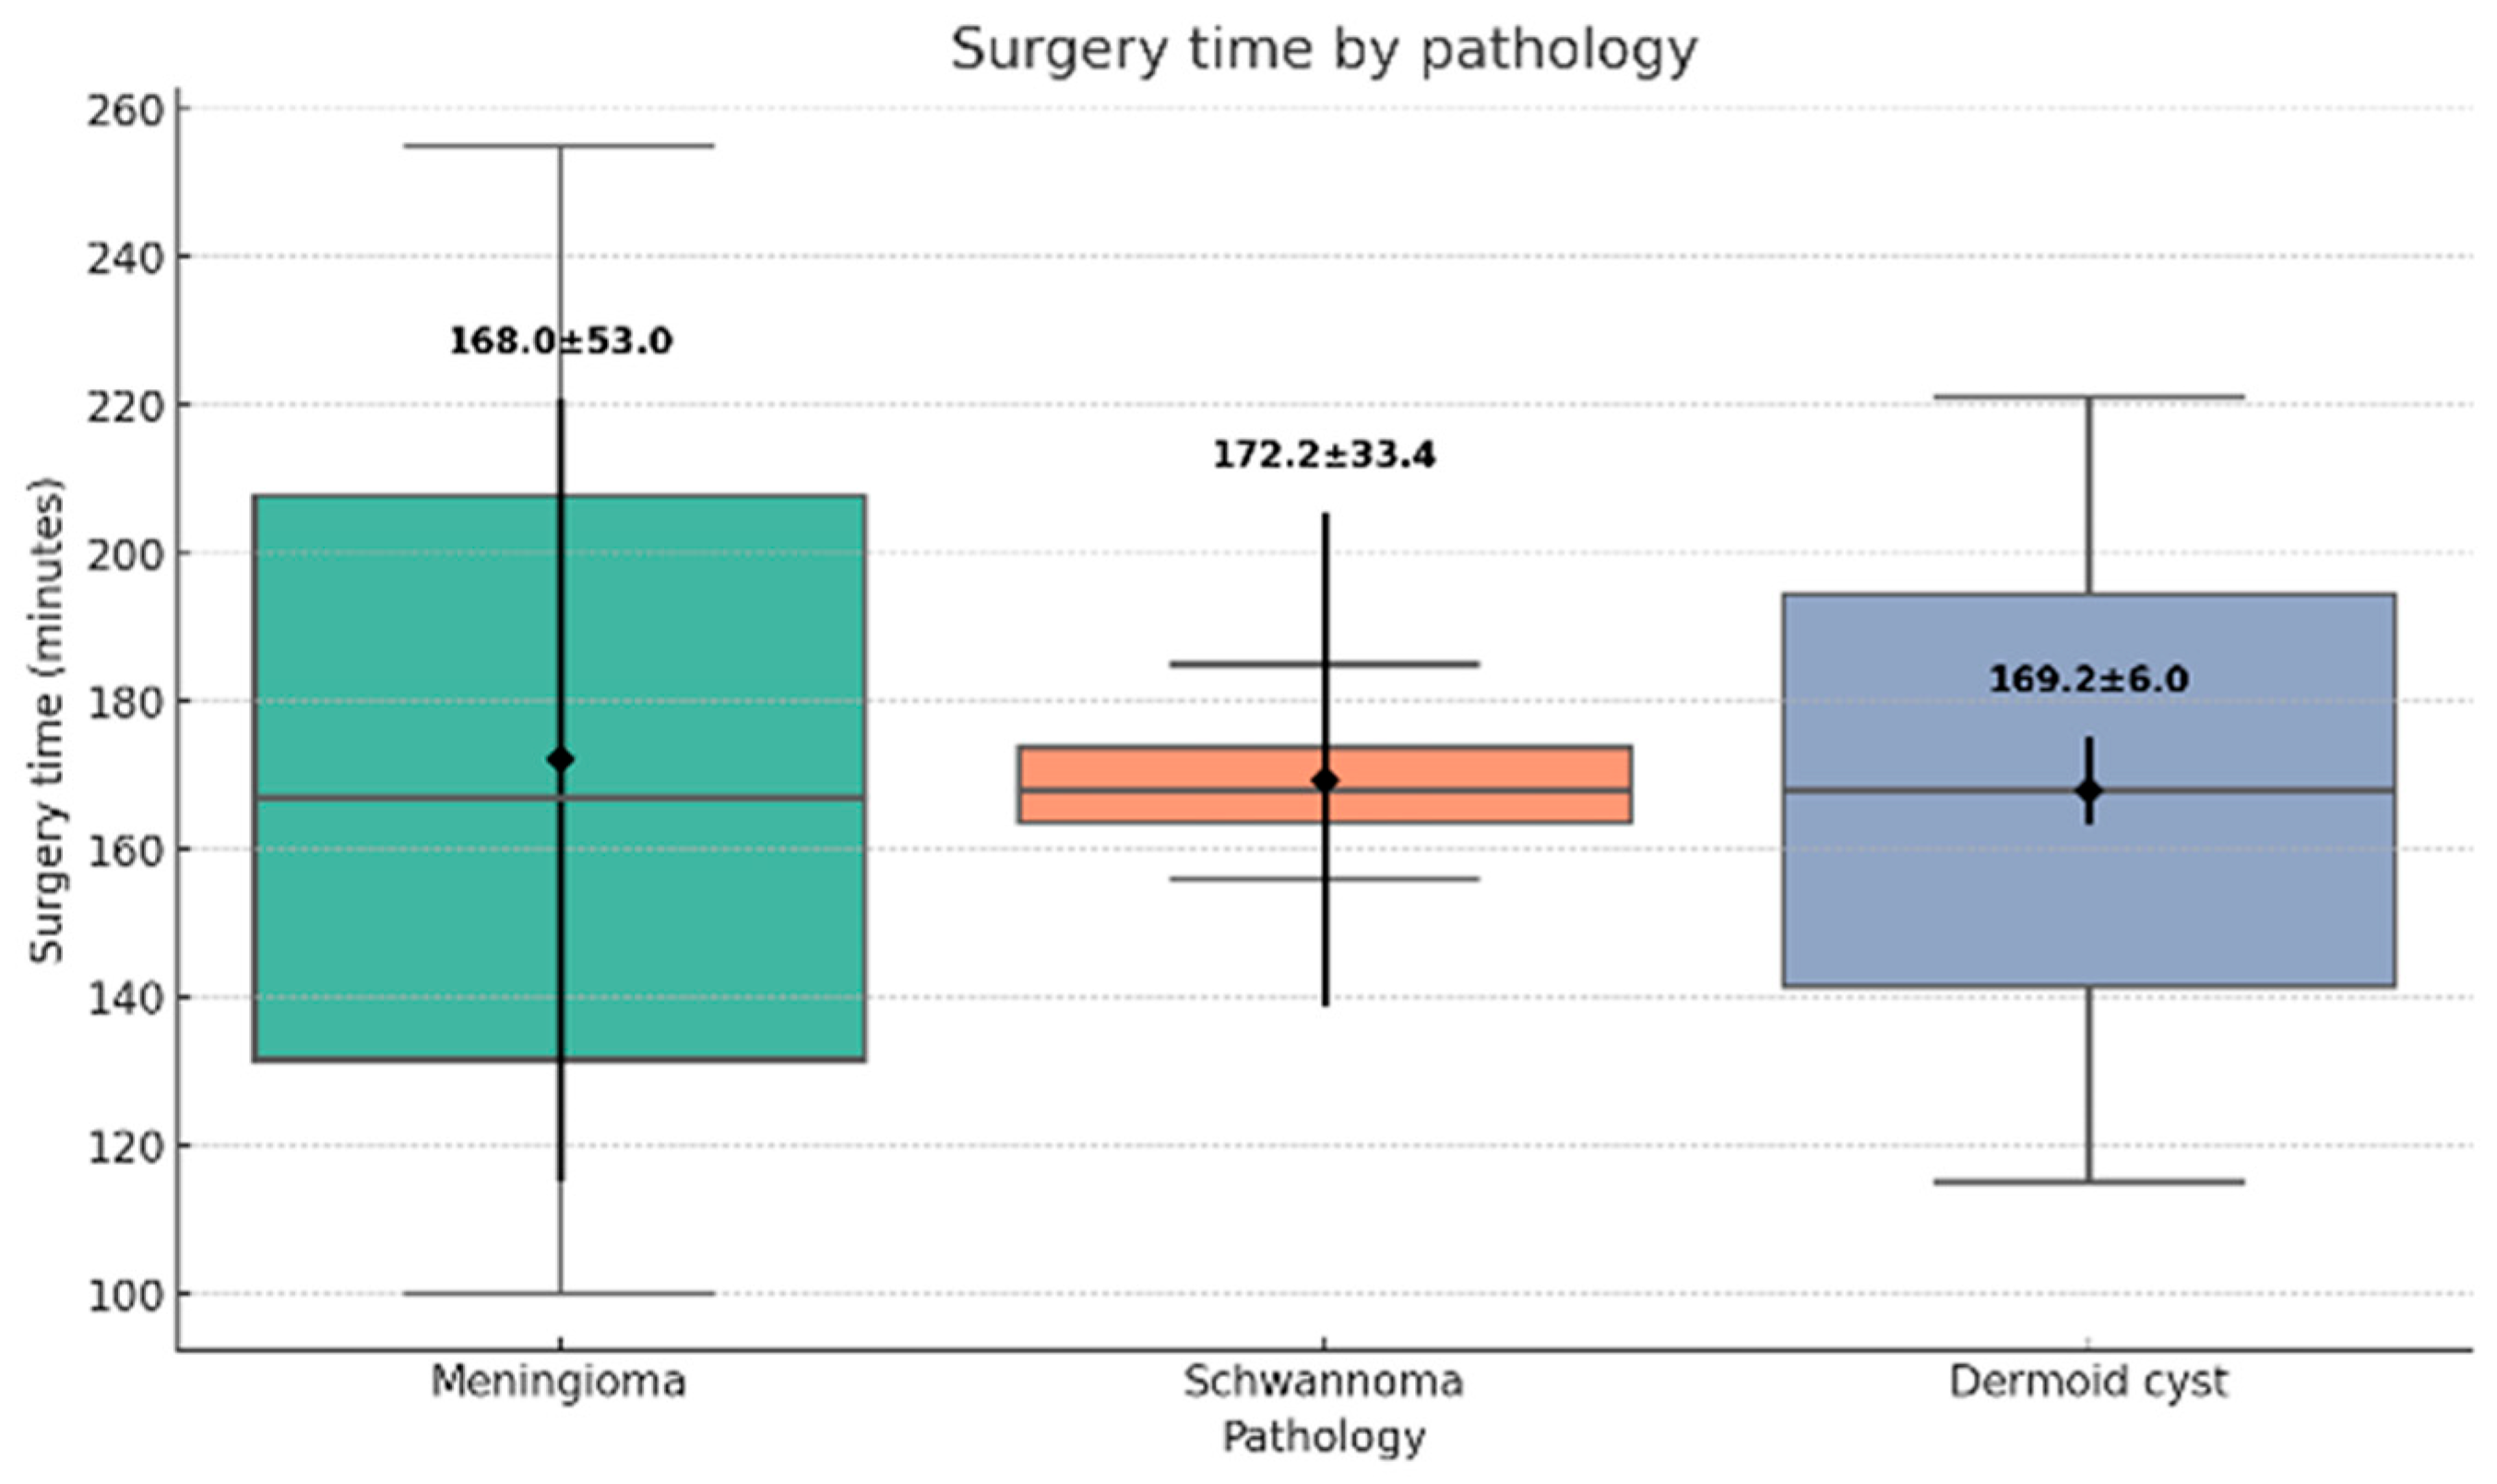

3.2. Surgical Outcomes and Complications

All surgical procedures were successfully completed via the UBE technique, with no conversions to open surgery. The mean operative time was 168.5 ± 24.3 min (range: 100–200 min) (

Figure 4). Estimated operative blood loss averaged 48.1 ± 12.7 mL (range: 30–70 mL) (

Figure 5).